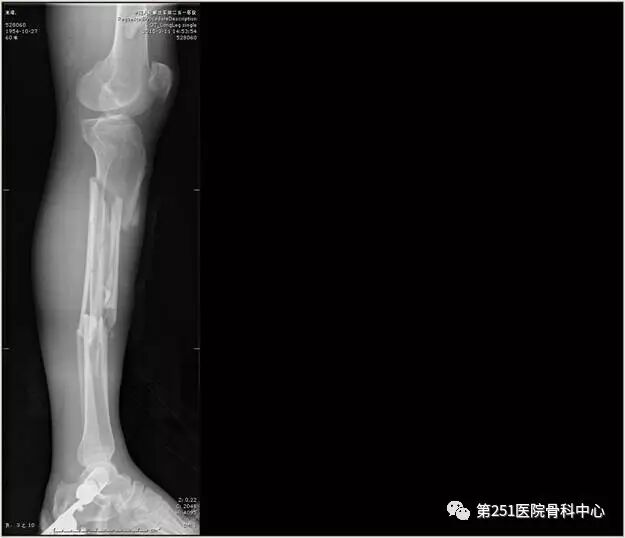

病例1:男性,40岁,车祸伤,胫腓骨多段骨折。

![]()